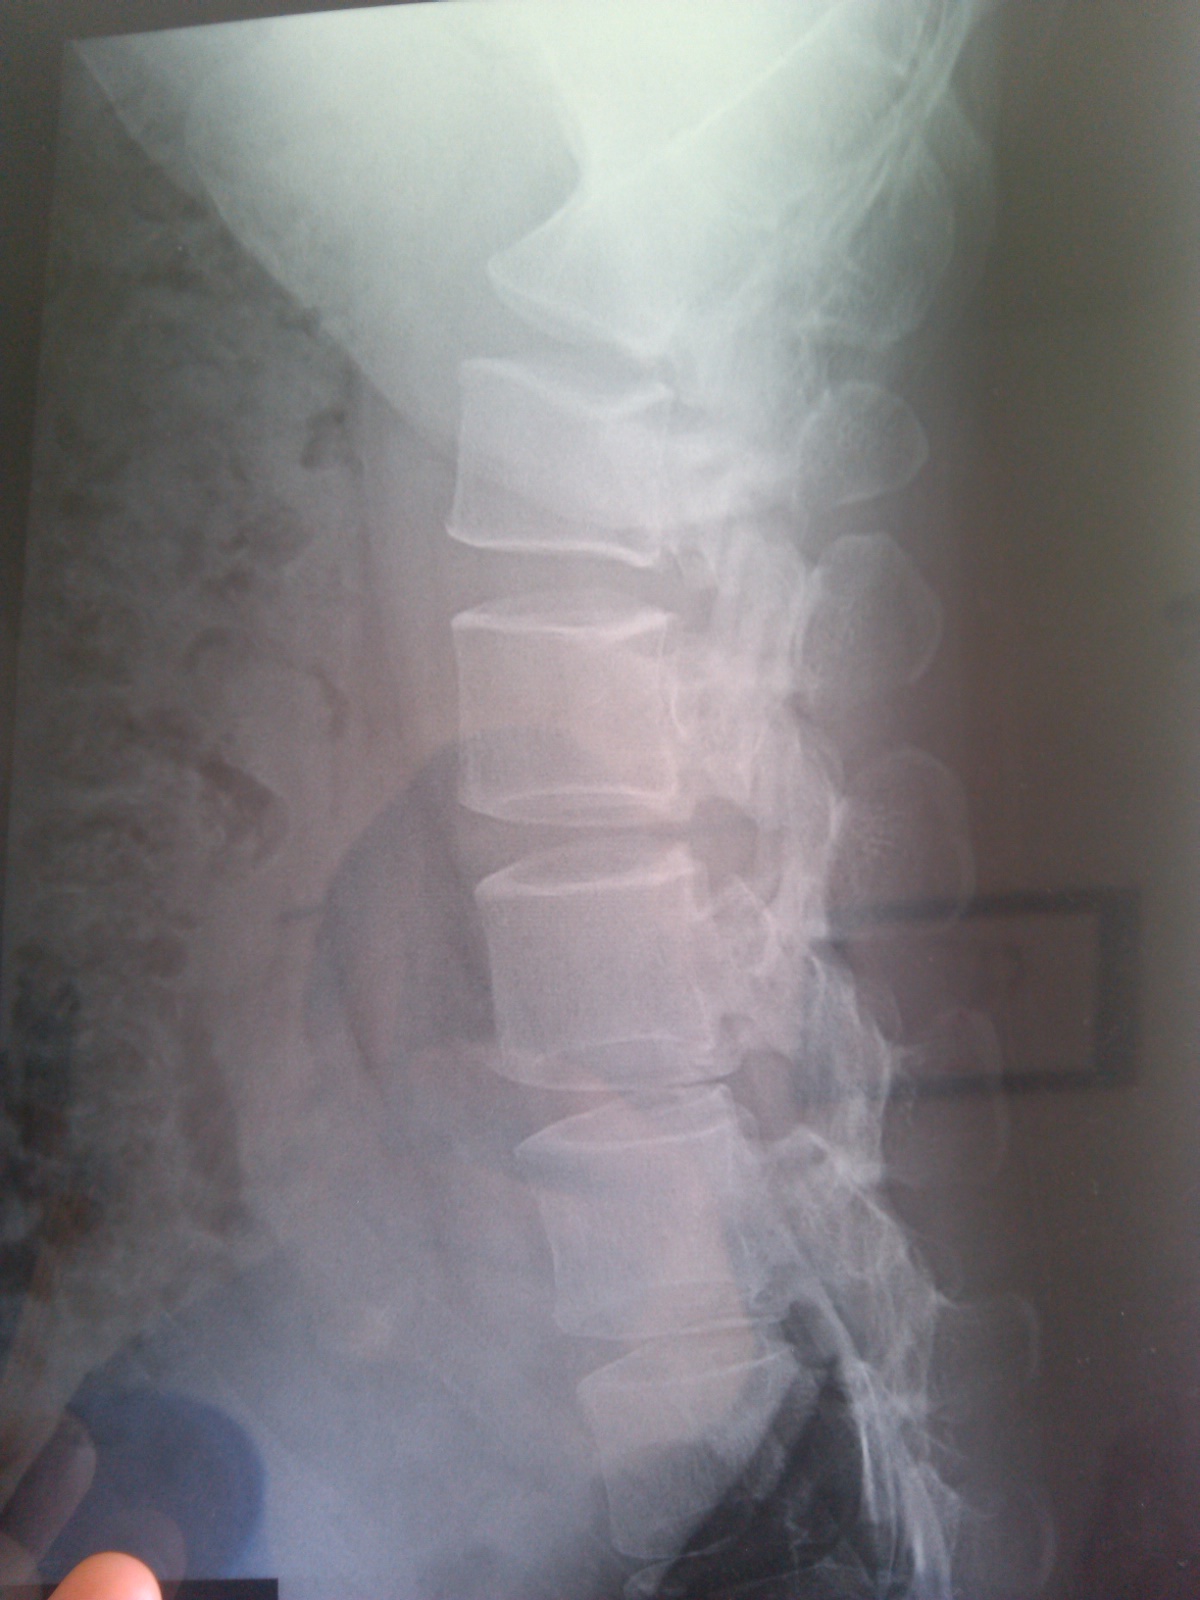

大家帮忙看看我这严重么,医生说只有手术,好害怕

帮忙看看好么,医生说只有手术,保守治疗行么

能帮忙看看么,做操管用么